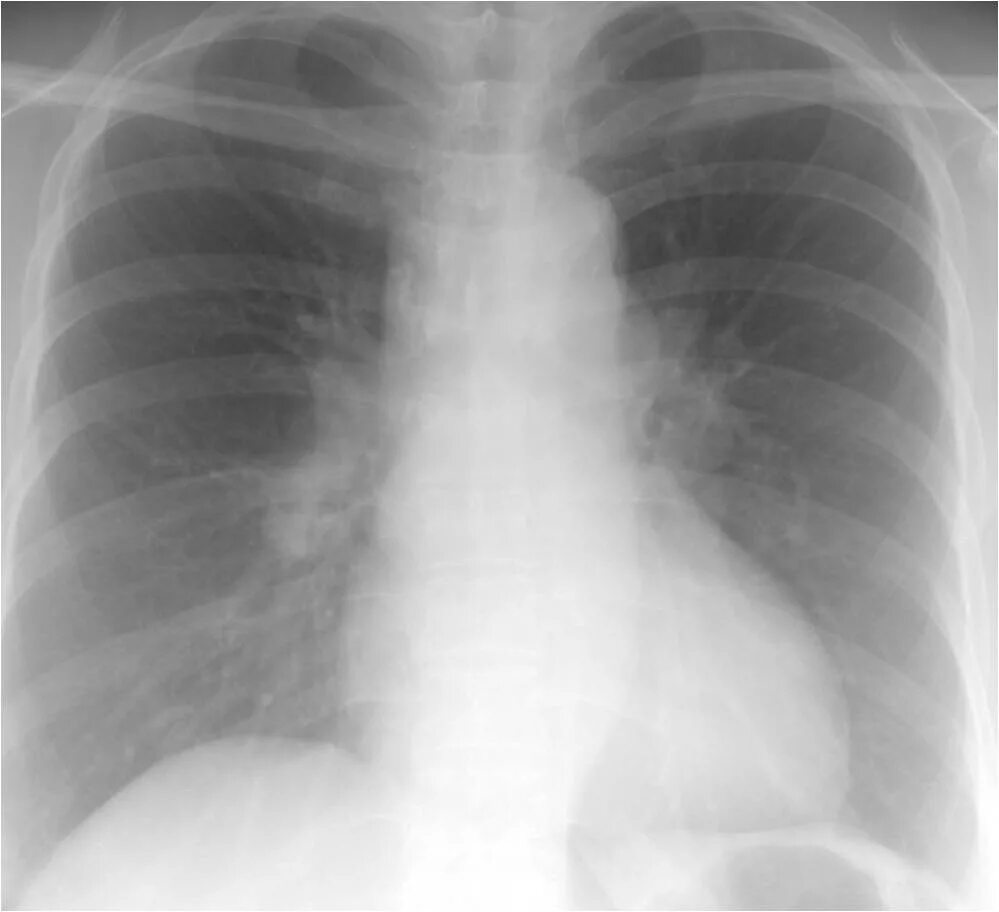

Фиброзное изменение левого легкого